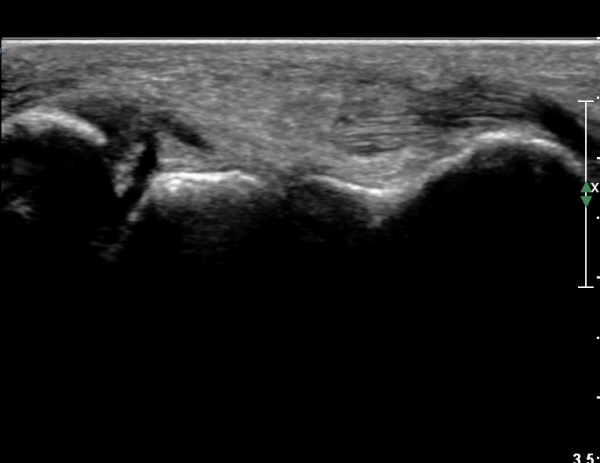

Àü¹æ¸»´ÜÁ¾°ñºñ°ñÀδë Á¾´Ü¸é°Ë»ç¿¡¼­ ƯÀÌ ¼Ò°ßÀ» º¸ÀÌÁö ¾ÊÀ½(»çÁø 1).